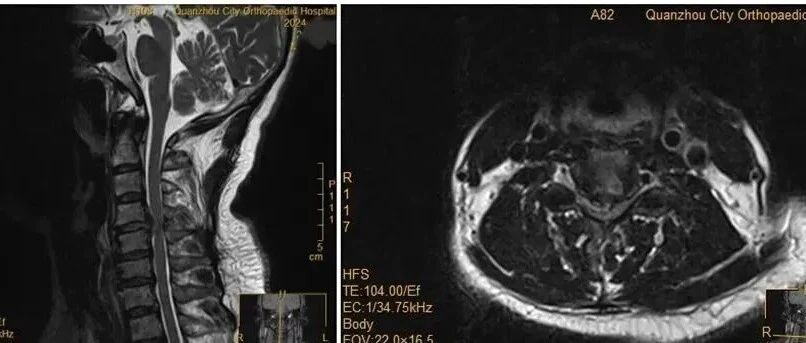

49岁男演员自曝已写好遗嘱,医生提醒:这类病日益年轻化...... 徐州新闻 · 21 小时前 |